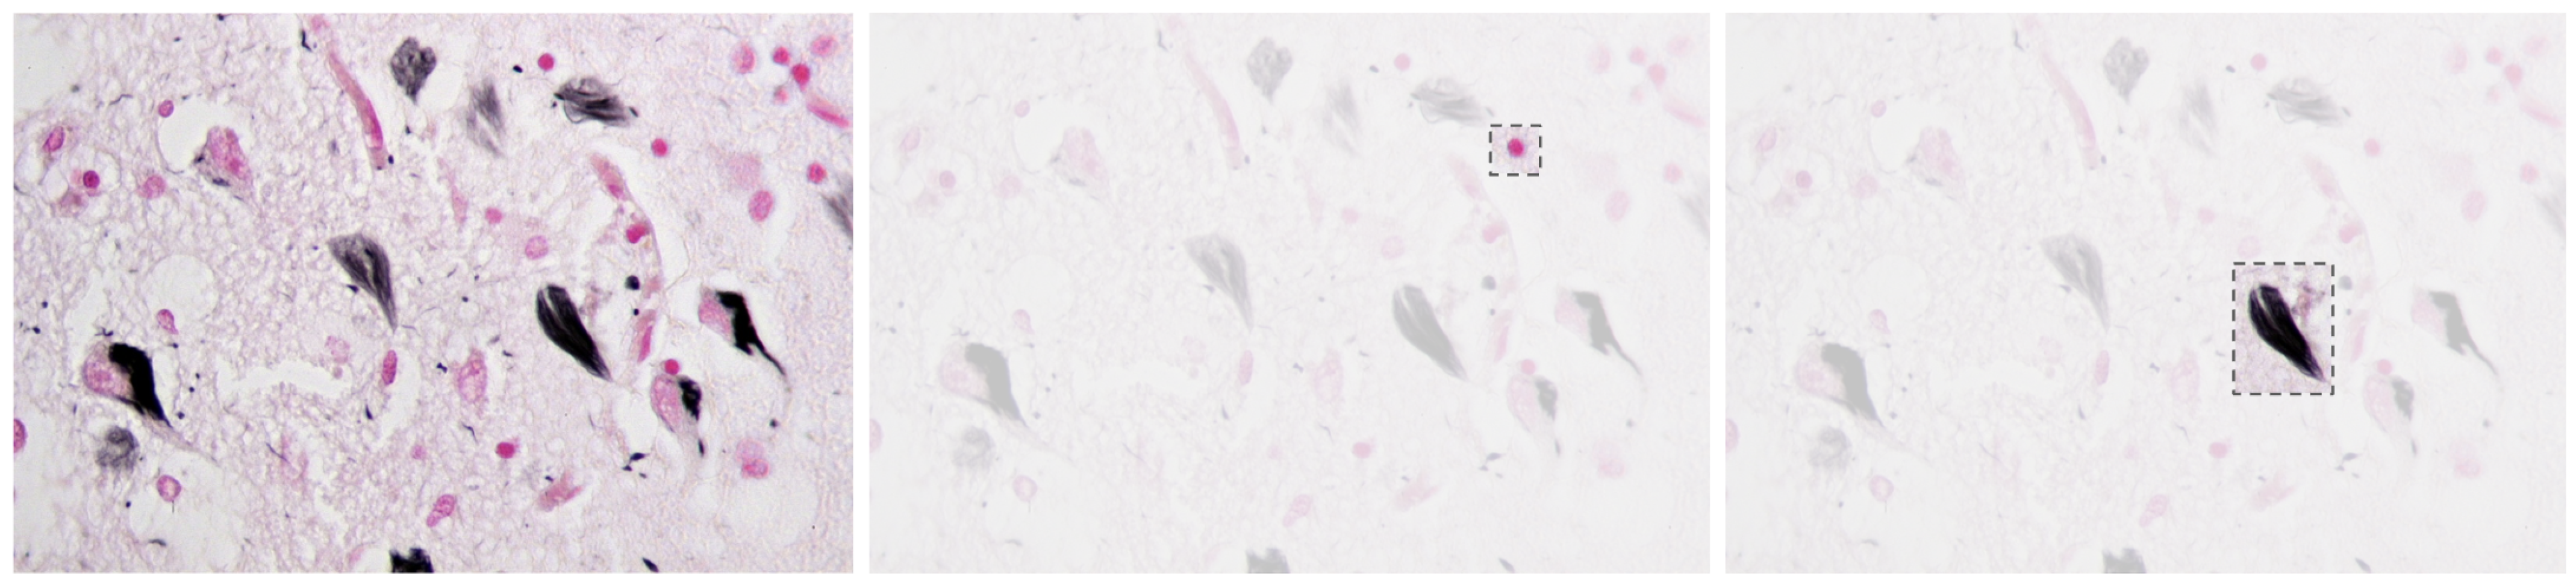

Alzheimer’s Disease (AD) is a progressive neurodegenerative disorder that causes amnesia, aphasia, and cognitive decline [1], among other symptoms. The neuropathology of AD is marked by cerebral atrophy caused primarily by the accumulation of two abnormal proteins: beta-amyloid (A) and tau [2,3]. Beta-amyloid aggregates extracellularly into plaques that disrupt neuronal communication, with the beta-amyloid 42 variant forming especially early and contributing significantly to the disease’s progression [1,4]. Concurrently, tau proteins missfold and accumulate intracellularly into neurofibrillar tangles, impairing axonal transport and contributing to synaptic dysfunction and neuronal death [2,5,6]. Figure 1 presents a histological section of brain tissue with Alzheimer’s markers, highlighting the characteristic amyloid plaques and neurofibrillar tangles, which are the hallmark pathological features of the disease.

Figure 1.

Alzheimer’s brain tissue with amyloid plaques (pink) and neurofibrillary tangles (black) [7].

Together, these pathological features degrade the neural networks of the brain and contribute to the clinical symptoms of the disease [8,9].